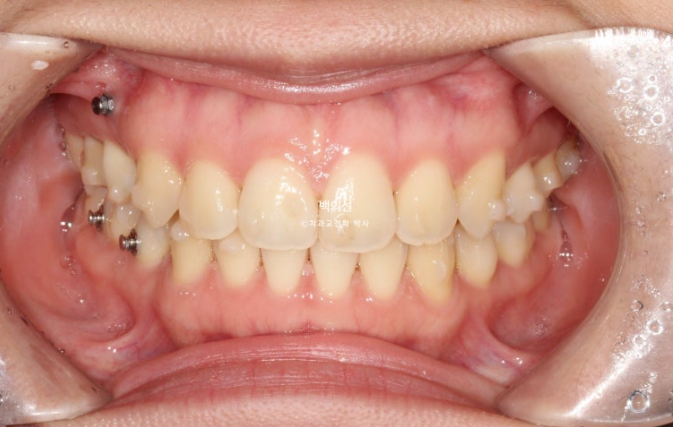

23.01~25.07

중심선은 정확히 맞으며

맞아진 중심선과 개선된 앞니 개방교합. 이제 면 편하게 끊어 드실 수 있겠어요.